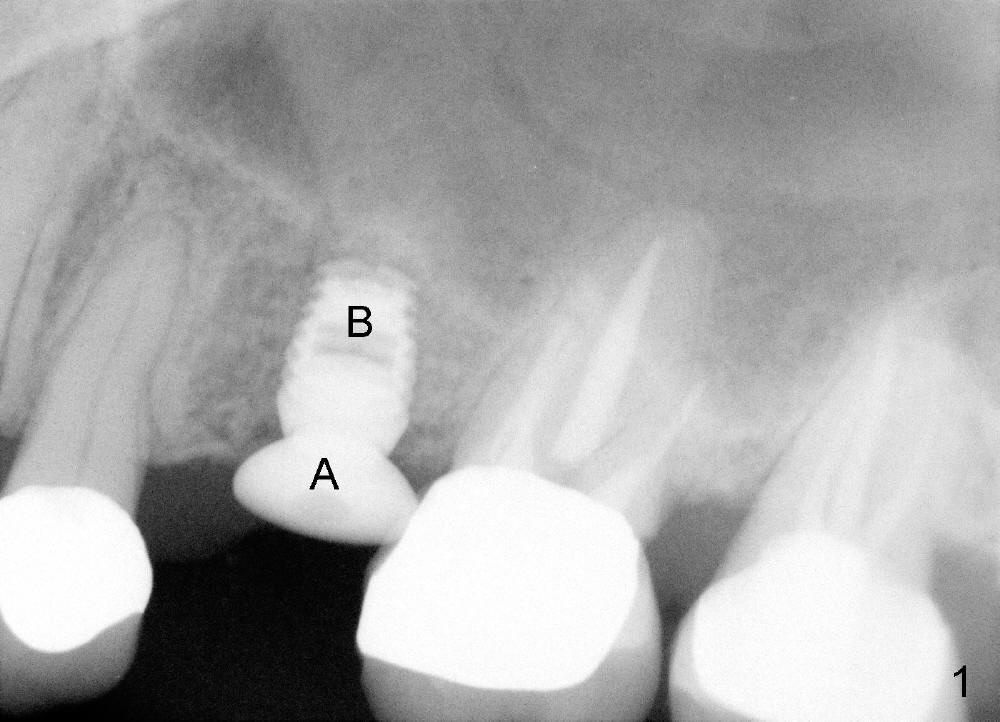

A 59-year-old lady used to have a 3-unit bridge in the upper left quadrant. A 4.5x6mm Bicon implant (Fig.1 B without extruding into the sinus) was placed in the atrophic pontic area 5 months earlier. When the abutment (A) was removed, the implant came out. The osteotomy was processed with a 4.5x14 mm tapered tap, which was unstable. When a 4.8 mm cylindrical tap was placed (past the sinus floor), it was tight (Fig.2). A 5x14 mm cylindrical implant (Fig.3 I) was inserted with elevation of the apparent sinus floor (>, no allograft used in case of sinus infection). Seven months postop, the density of sinus floor increases (Fig.4 <). The implant is stable and processed for crown (Fig.5 C, different view of the lifted sinus floor (<)). While sinus floor density is decreasing, the mesial and distal bone density is increasing 6 months (Fig.6), 1 year 6 months (Fig.7) and 3 year 6 months (Fig.8) post cementation.

It appears necessary to engage an implant into the sinus floor for primary stability for a skinny, probably osteoporotic female patient. The shape and diameter of the implant are also critical.